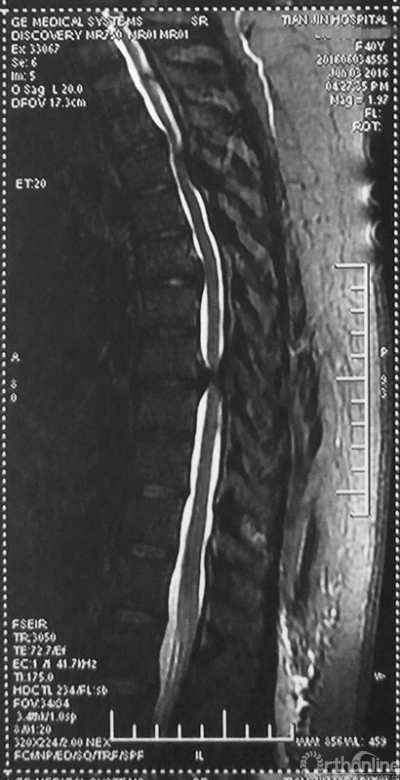

术后CT

最终,由任万陆主任亲自为患者进行了全身麻醉,苗军主任为其实施了后路的胸8-10椎板减压术,手术麻醉过程平稳,手术出血不多,术后不仅没有截瘫,神经功能进一步恢复,好转出院。术后一个月随访,患者已经可以扶助行器行走,患者对疗效非常满意。